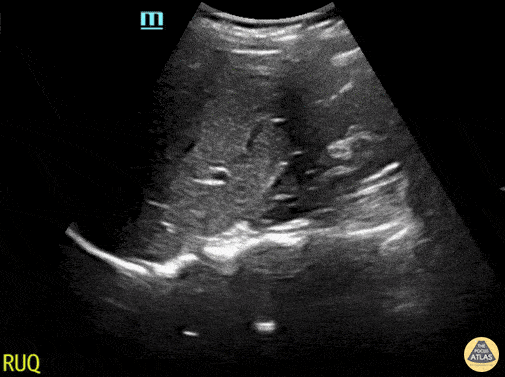

Peds-Trauma

abnormalluq, abnormalruq, msk, traumanormal